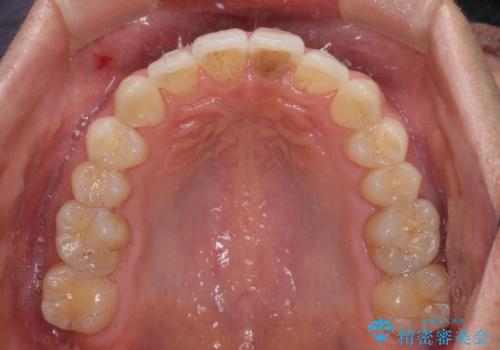

矯正治療後、前歯の形と色が気になるとのことでしたが、大分前に失活している(神経が取り除かれている)歯であり、その影響で変色しているため、オールセラミッククラウンによる補綴治療をおすすめいたしました。